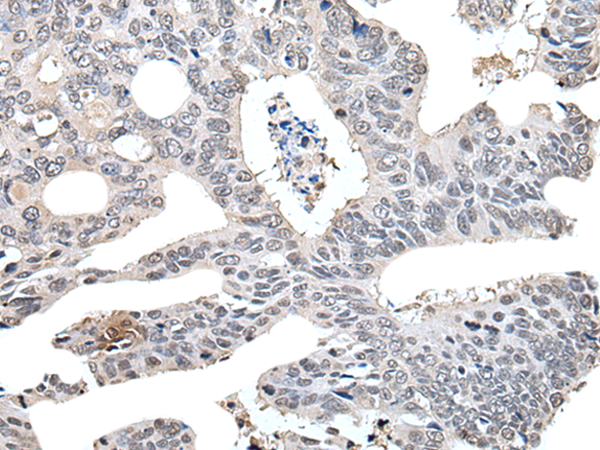

IHC positive control: |

Human colorectal cancer |

IHC Recommend dilution: |

30-150 |